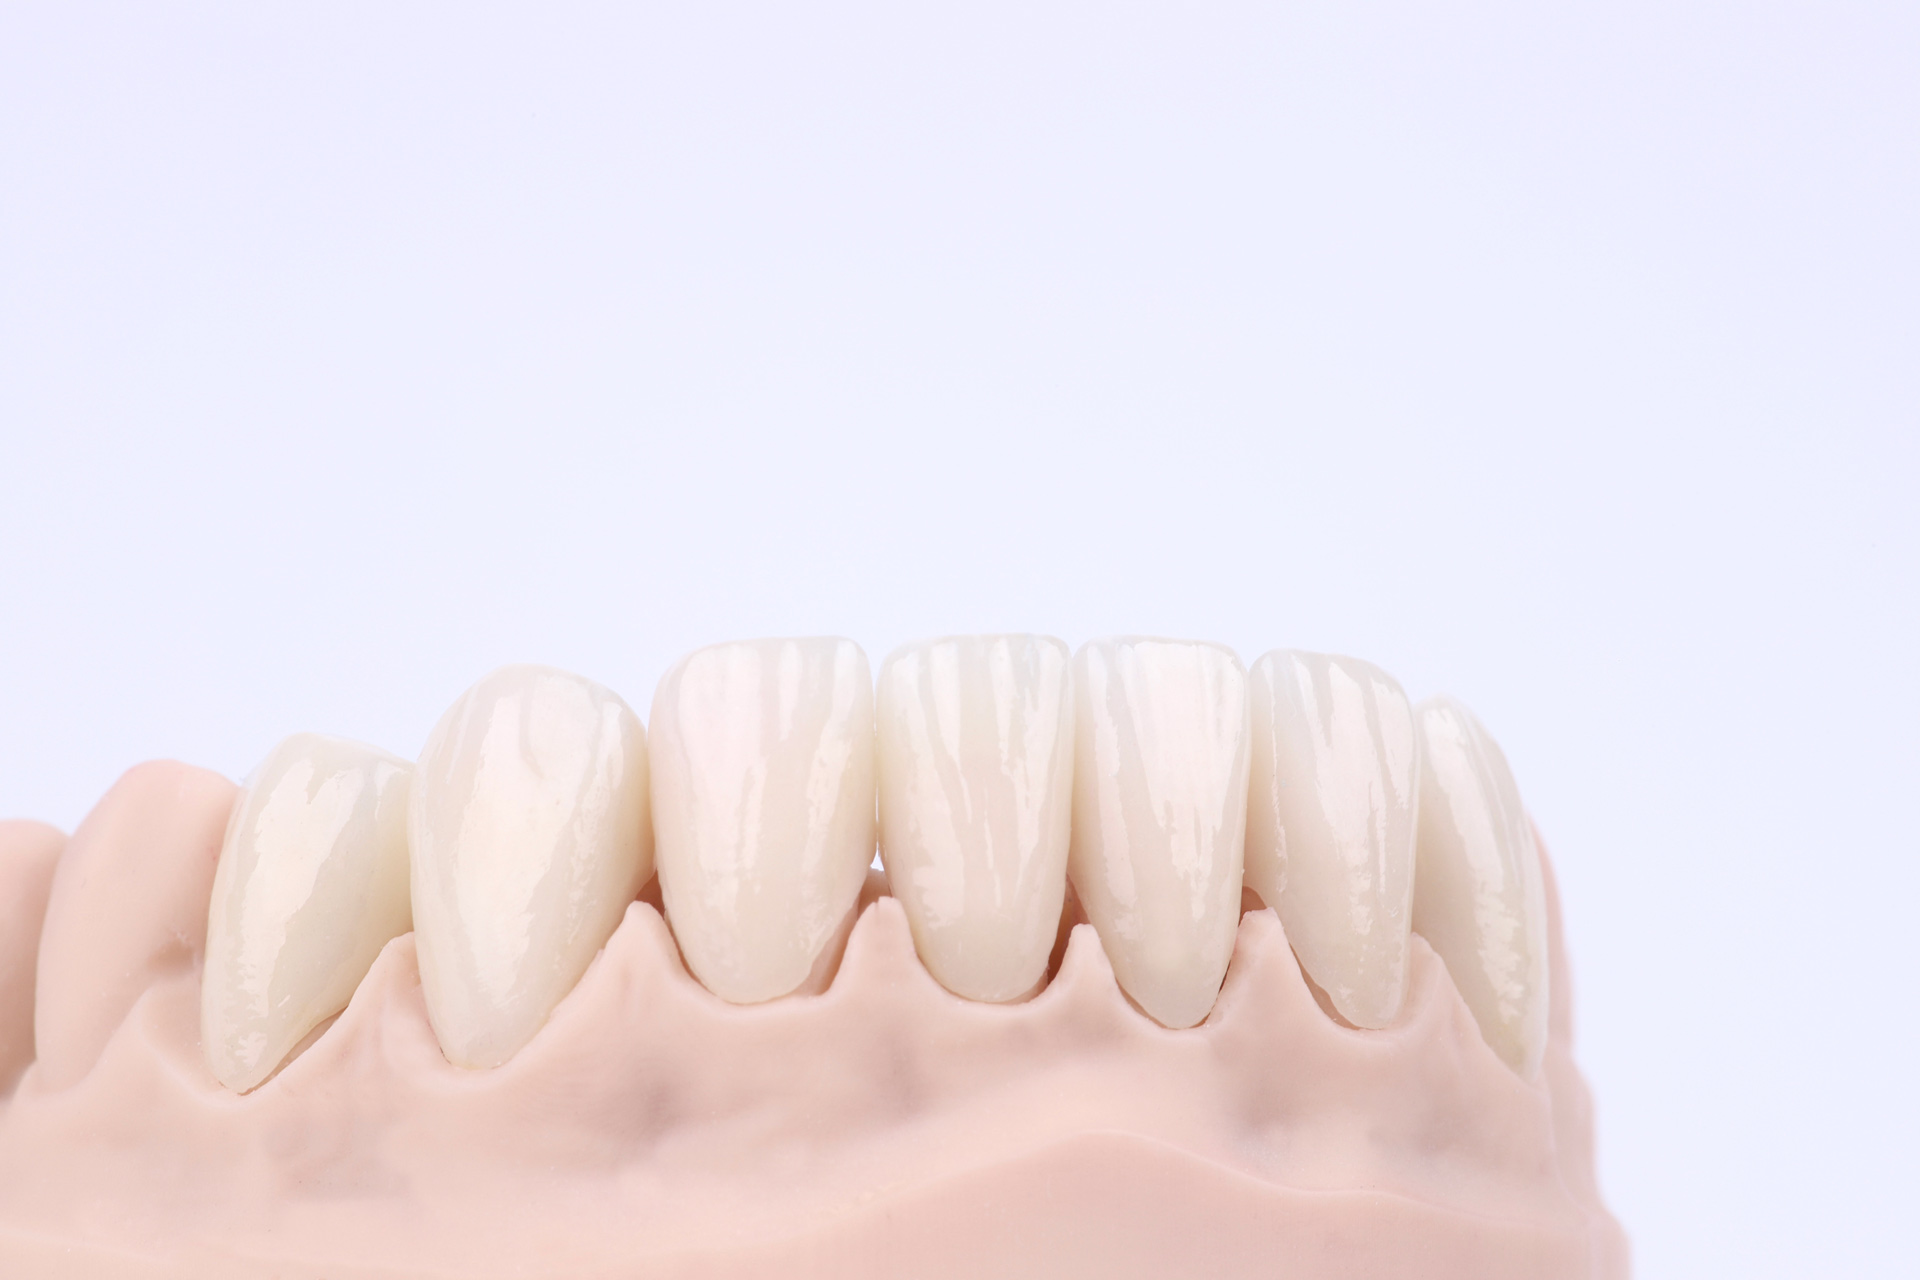

І настала війна… Після 1,5 року ми зустрілись знову. А частини тимчасових зубів вже не було, але положення щелеп та імплантанти збереглись. Тому дуже швидко перевели роботу з тимчасових коронок на постійні. Загалом було встановлено всі види ортопедичних конструкцій: коронки, вініри та керамічні накладки.